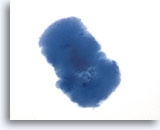

FNA van de schildklier wordt verkregen door sturing via palpatie of ultrasound, afhankelijk van de grootte van de laesie. Beide methoden worden op dezelfde manier afgehandeld, dat wil zeggen dat conventionele directe uitstrijkjes van de aspiraties worden gemaakt, of dat het aspiraat in een preservatief wordt gespoeld, waarmee een vloeibaar preparaat wordt gemaakt. Twee studies waarbij de nauwkeurigheid van ThinPrep® preparaten werd vergeleken met conventionele uitstrijkjes voor schildklier FNA, hadden als conclusie dat de nauwkeurigheid van deze twee methodes voor schildklierneoplasma vergelijkbaar was,[3, 4]hoewel een van de onderzoeken uitwees dat ThinPrep preparaten een lagere algehele correlatie met de histologische diagnose hadden dan directe uitstrijkjes, vooral bij het opsporen van chronische lymfocytische thyroïditis (62% voor ThinPrep tegen 92% voor directe uitstrijkjes). [4] Bovendien suggereerden enkele auteurs dat bij ThinPrep preparaten detectie van diffuus of waterig colloïd niet mogelijk is.[3, 5] In een studie van Tulecke et al bleek dat tissue-achtig materiaal op ThinPrep geassocieerd was met overvloedig colloïde materiaal bij histologie; dit vertegenwoordigt waarschijnlijk waterig colloïd. [6] Alles bij elkaar lijkt het erop dat colloïde kwantitatief minder aanwezig is op ThinPrep dan op conventionele uitstrijkjes. ThinPrep is echter superieur aan conventionele uitstrijkjes, of deze nu gefixeerd zijn in alcohol of luchtgedroogd, wat betreft het aantonen van kerneigenschappen die essentieel zijn voor de diagnose van papillair carcinoom. ThinPrep echter lijkt follikels te fragmenteren. Hierbij worden folliculaire cellen veel sneller gepresenteerd in lagen, groepen of zelfs los dan op conventionele uitstrijkjes.